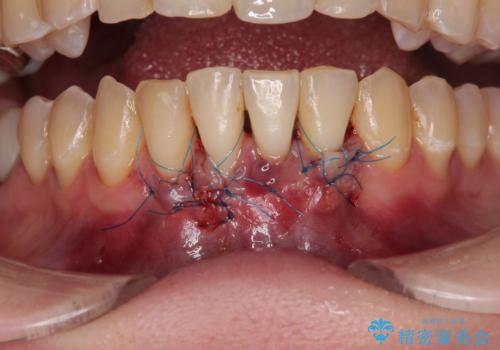

歯肉退縮に対して、上顎からの結合組織移植術(CTG)により、歯根の被覆を行うとともに、歯肉の厚みを増すことで将来の退縮リスクを抑制することとしました。

一度の処置で大幅に露出部の被覆に成功しましたが、更なる厚みと被覆を希望されて2回目の処置を行いました。